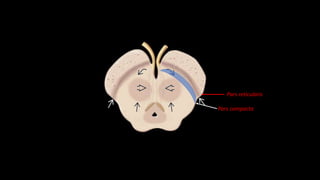

Substância nigra

Pars reticularis

Pars compacta

Núcleos vermelhos

Núcleo subtalâmicoNúcleo subtalâmico